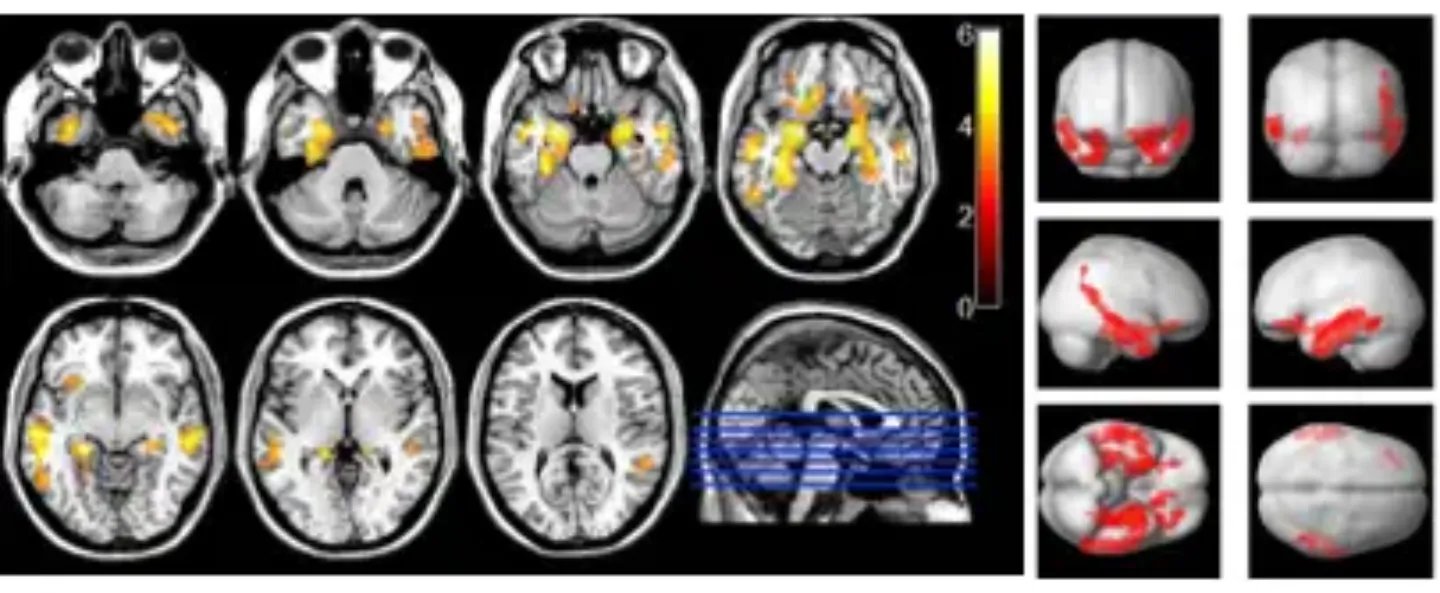

Figure 2: Regions of gray matter atrophy in patients with Mild Cognitive Impairment compared with healthy control subjects.

Figure 3: Regions of gray matter atrophy in patients with AD compared with healthy control subjects.

Figure 4: Regions of hypoperfusion in patients with Mild Cognitive Impairment compared with healthy controls.

Figure 5: Regions of hypoperfusion in patients with AD compared with healthy controls.